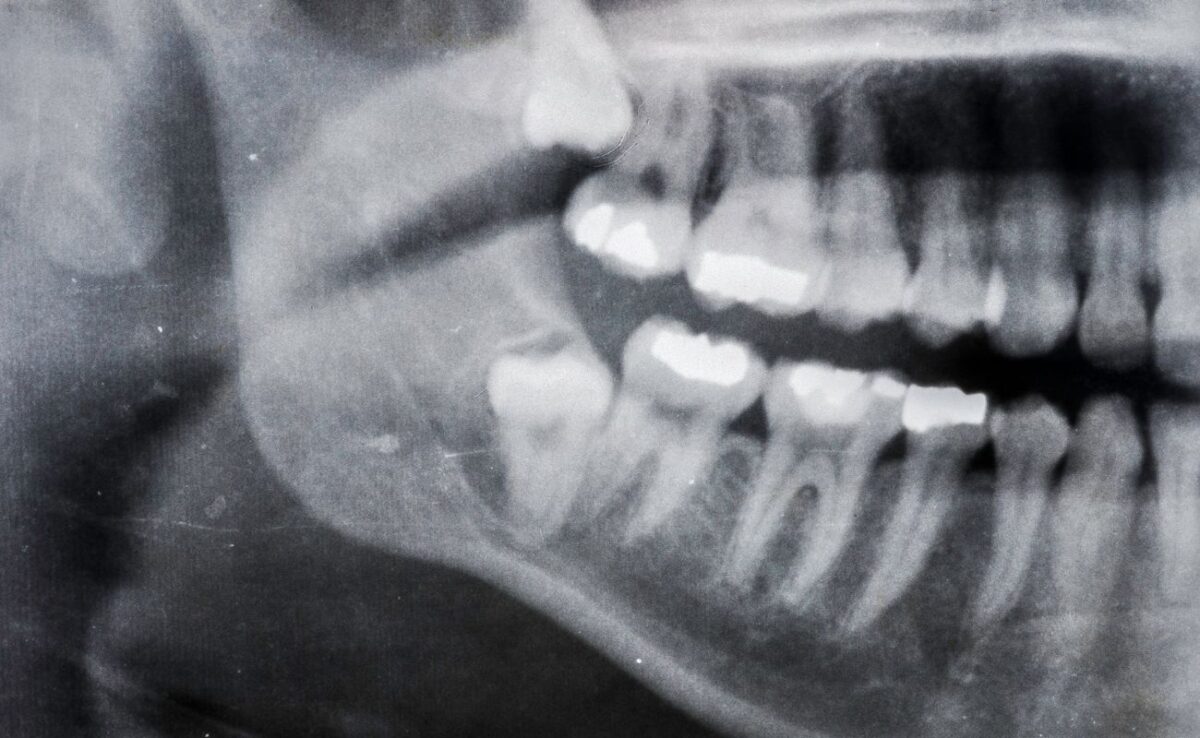

El diagnóstico de la atrofia ósea se realiza a través de un examen clínico completo y el uso de imágenes radiográficas, como las radiografías panorámicas o tomografías computarizadas (TAC). Estas imágenes permiten al dentista evaluar la cantidad de hueso perdido y planificar el tratamiento adecuado. En la Clínica Dental Equipo de la Torre, utilizamos tecnología de vanguardia para obtener diagnósticos precisos y personalizados para cada paciente.